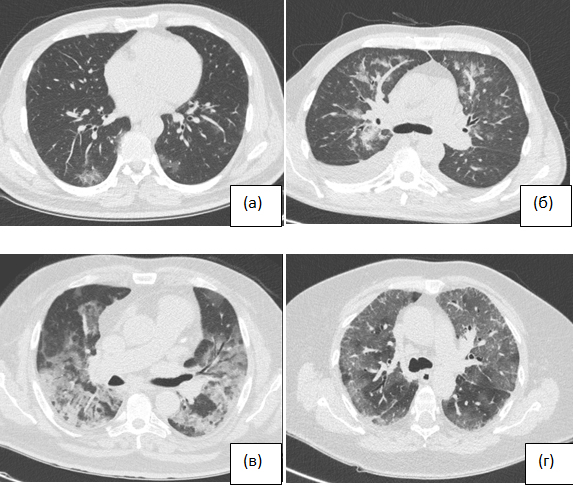

BACKGROUND: The 2019 coronavirus disease outbreak (COVID-19) quickly swept the world in just a month. Polymerase chain reaction (PCR) is used in the diagnosis of this disease, but this test has limitations related to false negative results, as well as PCR is a time-consuming procedure. Under these conditions, chest computed tomography (CT) can become one of the main methods in the Clinician’s Arsenal used for early detection of COVID-19 in patients who first seek medical help.

AIMS: comparison of the frequency of community-acquired pneumonia and its characteristics according to CT data before and during the COVID-19 epidemic and study of the possibilities of their timely detection and differential diagnosis.

MATERIALS AND METHODS: A retrospective analysis of chest CT scans results was performed in Davydovsky hospital (Moscow) from April 1 to April 17, 2020. It included all patients diagnosed with viral pneumonia at the CT. All patients with suspected diagnosis of viral pneumonia underwent PCR testing. Retrospective analysis of chest CT data from patients admitted to the hospital with suspected pneumonia for the same period in 2019 was taken as a comparison group.

RESULTS: For the period from April 1 to April 17, 2020 according to chest CT, pneumonia was diagnosed in 140 cases, of which 65 (46.4%) were described as viral, compared with the same period in 2019 − 7 diagnoses of viral pneumonia (10.3%) were described a significant increase in cases of viral pneumonia (5.723; p <0.01). Results of PCR test in patients with viral pneumonia according to CT data was: positive in 34 (52.3%), negative in 22 (33.8%), 9 (13.9%) patients were not tested. When comparing the frequency of detection on CT of viral pneumonia patterns in patients for the same period of time in 2019 and 2020, no significant differences were found. The probability of COVID-19 due to results of chest CT was: average 13.8%, high − 75.4%. The severity of viral pneumonia according to CT data was: light 38.5%, medium 46.2%, severe 12.3%, extremely severe 3.1%.

CONCLUSIONS: Rapid CT diagnostics of COVID-19, even with false negative results of PCR tests, can help to isolate a patient with suspected COVID-19, start treatment on time and prevent the further spread of viral infection in a pandemic. Nevertheless, due to the non-specificity of the revealed picture, the possibilities of CT to identify lung lesions by specific viral agents are limited.